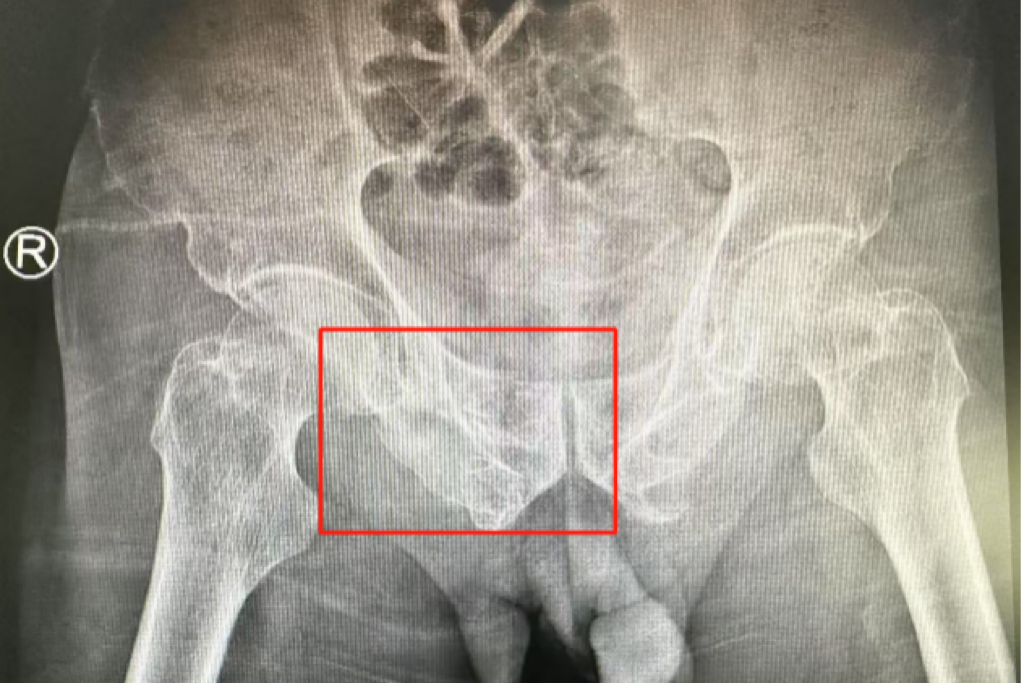

ÊõǰӰÏñѧÏÔʾ£¬»¼ÕßµÄ×ó²à÷¾¹Ç¹ÇÕÛ£¬ÓÒ²à³Ü¹Ç¹ÇÕÛ¡¢÷ĹǹÇÕÛ£¬¹ÇÅè¹ÇÕÛ·ÖÐÍΪCÐÍ£¬ÍíÄê´àÐÔ¹ÇÅè¹ÇÕÛ·ÖÐÍΪIVÐÍ£¬ÊǼ«¶Ë²»ÎȹÌÐ͵Äǰ»·¹ÇÕÛºÍË«²àºó»·¹ÇÕÛ¡£ËùÐÒûÓÐÏÔ×ŵĹÇÅè³öѪ»òÄÚÔàËðÉ˵ÄÌåÏÖ¡£

ÊõºóµÚ¶þÌ죬ҽÉúÍŶӸ´²éXƬÏÔʾÂݶ¤Ö²ÈëλÖúÜÊÇÖª×㣬¹ÇÕÛ»ù±¾µÖ´ïÎȹ̸´Î»£¬Í¬Ê±£¬¸´²éµÄȫѪϸ°û¼ÆÊýÖУ¬ÑªºìÂѰ×Ö¸ÊýΪ102g/L¡£ÊõºóµÚÈýÌ죬ÔÚÖÇÄܹǿƲ¡·¿Õչ˻¤Ê¿ÍŶӼ°¿µ¸´Ê¦µÄÖ¸µ¼ºÍÕչ˻¤Ê¿Ï£¬Íõ´óÒ¯¿ÉÒÔ×øÁ¢ÔÚ´²ÉÏ¡£ÊõºóµÚËÄÌ죬Íõ´óÒ¯ÓÀ´Á˳öÔºÈÕ£¬¡°µÃ¿÷ÓÐÁËÕâôÏȽøµÄÒ½ÁÆÊÖÒÕ£¬ÈÃÎÒ»¹ÄÜϵØÐÐ×ߣ¬Ð»Ð»ÄãÃÇ£¡¡±

Âݶ¤Ö²ÈëλÖúÜÊÇÖª×ã